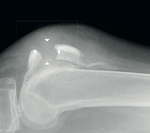

„Das war er also: der erste Season-Ender meiner Karriere! Alles ereignete sich letzten Januar beim Level-1-Trip nach Helsinki in Finnland. Wir filmten an einem Urban Rail. Bei einemVersuch erwischte ich die letzte Querstange des Rails und die schlug mir quasi direkt das Knie durch. Dabei zertrümmerte es mir die Kniescheibe komplett.

Nach diesem Trümmerbruch war die Saison natürlich vorbei und ich musste mich einer Operation unterziehen. Diese verlief zum Glück sehr gut, da ich in Dr. Kubiak einen der besten Trauma- Chirurgen hatte. Er hat die Sache von Anfang an realistisch betrachtet und war fest entschlossen, mich zu 100 Prozent wiederherzustellen. Ebenso wie ihm danke ich meinen Physiotherapeu- ten. Jeder Einzelne im Team hat unendlich viel Zeit in meine Rehabilitation ge- steckt. Nur so konnte die ohnehin schon schleppende Reha-Phase erfolgreich verlaufen. Bei einer Patellafraktur muss das Bein für mindestens zwei Monate in gestreckter Position ruhen, bevor die Physio überhaupt starten kann. Wenn es dann endlich so weit ist, sind die Muskeln natürlich total verkümmert und das Knie ist steif. Mein Bein ließ sich zu Anfang nur mit Mühe und Not bis zu einem Winkel von 30 Grad beugen. Nach fünf Monaten war ich immer noch damit beschäftigt, die Beugung meines Knies wiederherzustellen. Immerhin konnte ich dann wieder mit dem Lauftraining beginnen. Sobald die Flexibilität des Gelenks wieder einigermaßen vorhanden war, konnte ich mit dem Muskelaufbau beginnen. Eine harte Zeit, aber da musste ich wohl durch!